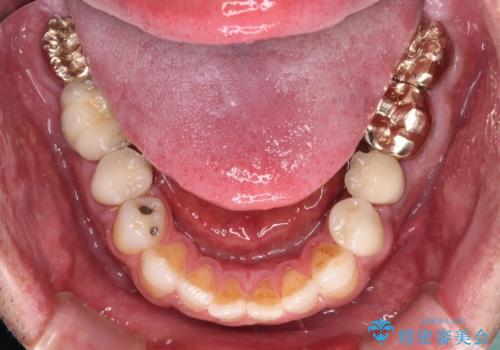

抜歯が必要な左右の奥歯 ブリッジとインプラントによる奥歯の補綴治療

左側は大臼歯2本と小臼歯1本が欠損しているため、インプラント2本を治療したブリッジ、右側は中間欠損であり、前後の歯も加療が必要であったためブリッジによる補綴治療を行うこととしました。

抜歯となった歯は全て神経が抜かれた歯であり、強大な咬合力によって破折したことが原因で抜歯となりました。

左右同時に強大な力を受けながらの治療であったため、仮歯の脱落や破損などがひんぱつしました。

治療後の現在は、より長い期間安定した状態を維持していただくため、就寝時マウスピースを装着するようお願いしております。